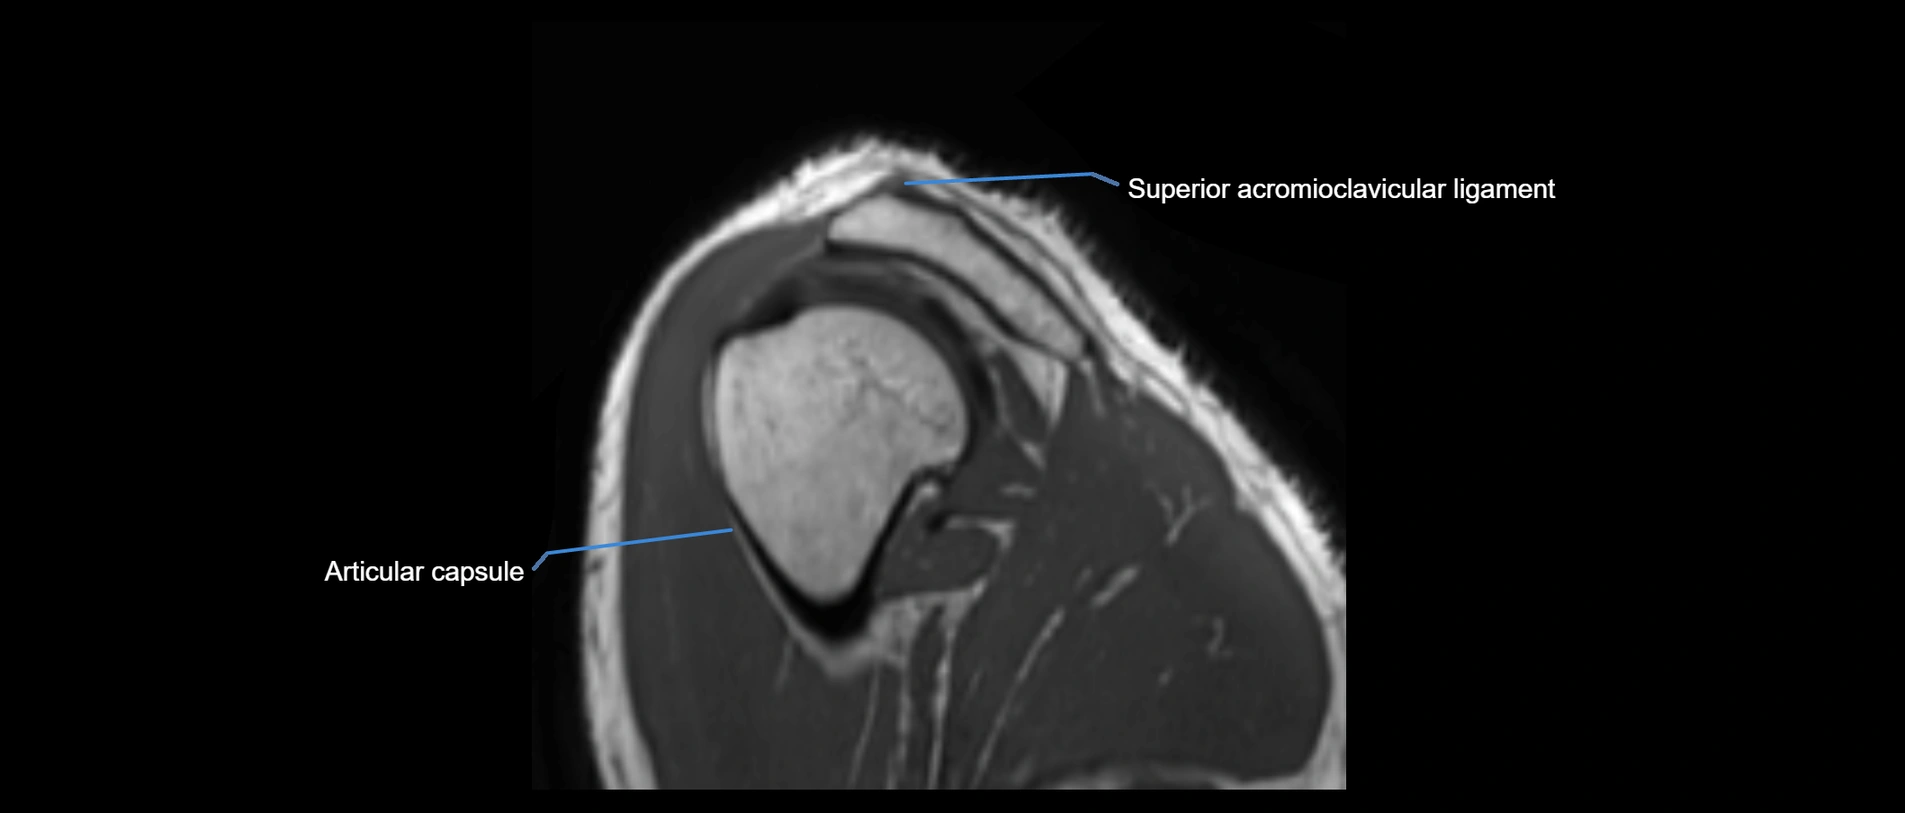

MRI Appearance

• T1-weighted images:

• Normal ligament: Low signal (dark linear band) spanning acromion to clavicle.

• Surrounding fat planes: Bright, delineating the ligament clearly.

• Marrow of clavicle and acromion: Bright due to fatty content.

• Tears: Discontinuity or irregular thickening with intermediate-to-bright signal.

• Chronic injury: Thinning, fraying, or irregular low-signal fibers with adjacent scarring.

• T2-weighted images:

• Normal ligament: Low signal, homogeneous.

• Partial tear or sprain: Focal hyperintensity or thickening.

• Complete tear: Discontinuity with fluid-bright gap between clavicle and acromion.

• Associated edema: Bright signal in distal clavicle or acromion marrow.

MRI images

image